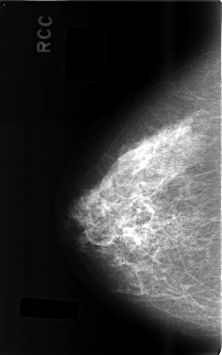

C_0487_1.RIGHT_CC

RIGHT_CC LINES 4608 PIXELS_PER_LINE 2880 BITS_PER_PIXEL 12 RESOLUTION 50 NON_OVERLAY